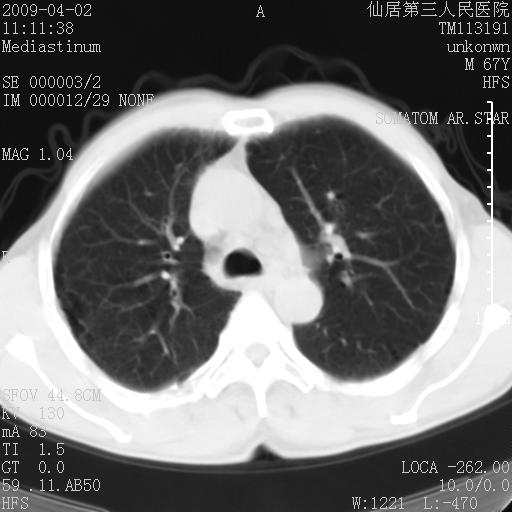

患者老年男性,乏力畏寒来诊,摄胸片示右下肺感染性病变,抗炎两周后复查胸片,无好转有进展。

后做ct平扫表现如下:

考虑右肺炎症可能性大,不除外细支气管肺泡癌

是否还要考虑肺间质纤维化,建议hrct扫描。

考虑间质性肺炎。

病灶呈蜂窝征,纵隔多个淋巴结肿大;肺泡癌需考虑

我认为普通的感染应该可以除外,间质性肺炎可能性较大,但如何解释纵膈的淋巴结肿大呢

考虑双肺间质性改变(间质纤维化?)伴右肺下叶感染。